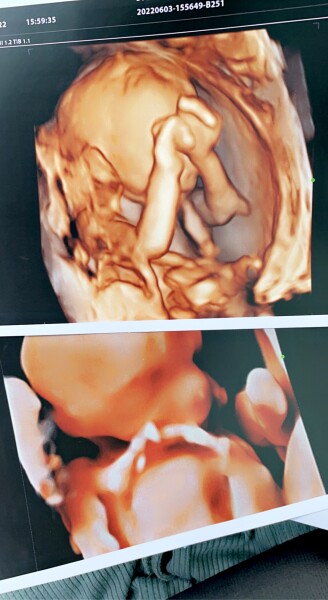

Kathno4 · 04/06/2022 20:45

18 + 3, 3d/4d scans yesterday ❤️

still feeling awful and hormonal but I’m sure it’s related to the antibody situation; I got my special blood card through the post today… to carry around at all times and make sure we get given the right blood if we need it, last time had 2 antigens this time have 3. Overthinking outcomes are shit. I’m not sleeping. counting down the days I have baby out of my womb and in my arms hopefully as healthy as can be, feel guilty and like my body is a failure 😣